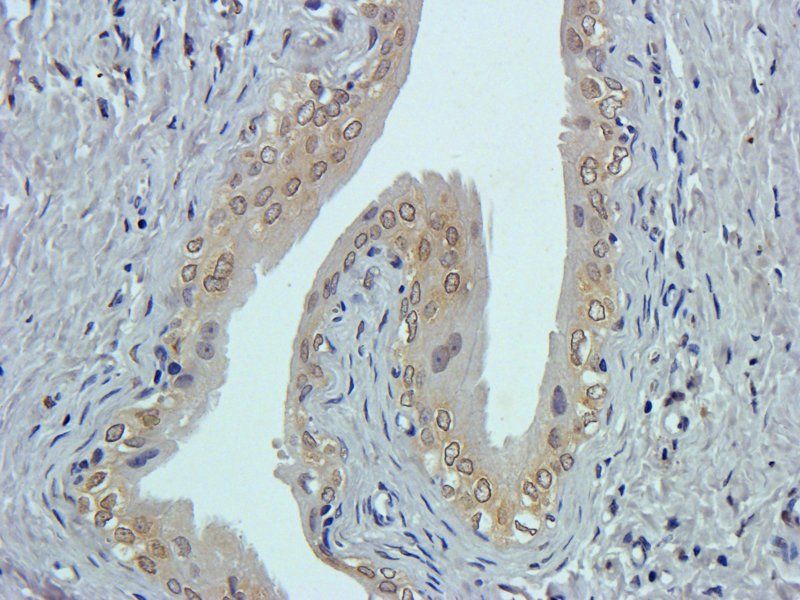

CD24 antibody

CD24. Recognizes endogenous levels of CD24 protein

IHC-P

应用稀释比例:IHC-P: 1:100-500 (based on 0.5 mg/ml)

Identification of Human Pancreatic Cancer Stem Cells

, prostate, ovarian, melanoma, colon, and breast cancers. We have recently reported the identification of a subpopulation of pancreatic cancer cells that express the cell surface markers CD44+CD24+ESA+ (0.2–0.8% of all human pancreatic cancer cells